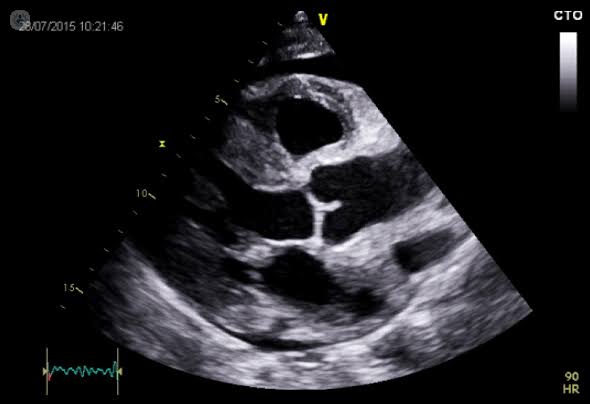

Echocardiography Sialkot

Unlocking the Insights of Echocardiography Sialkot: Understanding the Indications for an Echo Test of the Heart

Echocardiography is a non-invasive, painless imaging technique that uses high-frequency sound waves (ultrasound) to create detailed images of the heart. It allows healthcare providers to visualize the heart’s structure, size, and function in real-time. This diagnostic procedure plays a crucial role in the evaluation and diagnosis of various cardiac conditions.